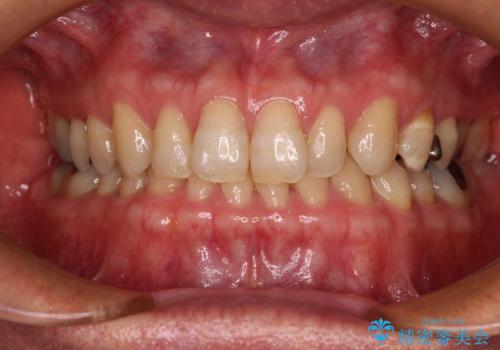

前歯のブリッジを綺麗に作り変えたい

- 前歯の突出感がきになり、ブリッジの作り替えを希望して来院された患者様です。

土台となる歯のうち、違和感のある歯については根管治療を行うこととしました。

口元の突出感を軽減するため、下の前歯をマウスピース矯正により引っ込め、その後オールセラミックブリッジにより補綴することとしました。

下の前歯の矯正治療に時間がかかりましたが、しっかりと内側に下げることができたので、ブリッジの突出感を大幅に改善することができました。

自然な仕上がりの前歯になるとともに、口元も引っ込めることができ、患者様には大変満足していただきました。